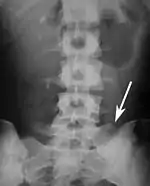

Sacralization of the L5 vertebra is seen at the lower right of the image.

Sacralization of the fifth lumbar vertebra (or sacralization) is a congenital anomaly, in which the transverse process of the last lumbar vertebra (L5) fuses to the sacrum on one side or both, or to ilium, or both. These anomalies are observed in about 3.5 percent of people, and it is usually bilateral but can be unilateral or incomplete (ipsilateral or contralateral rudimentary facets) as well. Although sacralization may be a cause of low back pain, it is asymptomatic in many cases (especially bilateral type). Low back pain in these cases most likely occurs due to biomechanics. In sacralization, the L5-S1 intervertebral disc may be thin and narrow. This abnormality is found by X-ray.